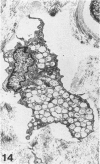

Five cats with feline alpha-L-iduronidase-deficient mucopolysaccharidosis were studied. Membrane-bound cytoplasmic inclusions were present in central nervous system neurons, hepatocytes, chondrocytes, vascular and splenic smooth muscle cells, bone marrow leukocytes, and fibroblasts of the skin, eye, and cardiac valves. The lesions in these cats closely resemble those described in human patients with mucopolysaccharidosis I H (Hurler syndrome).